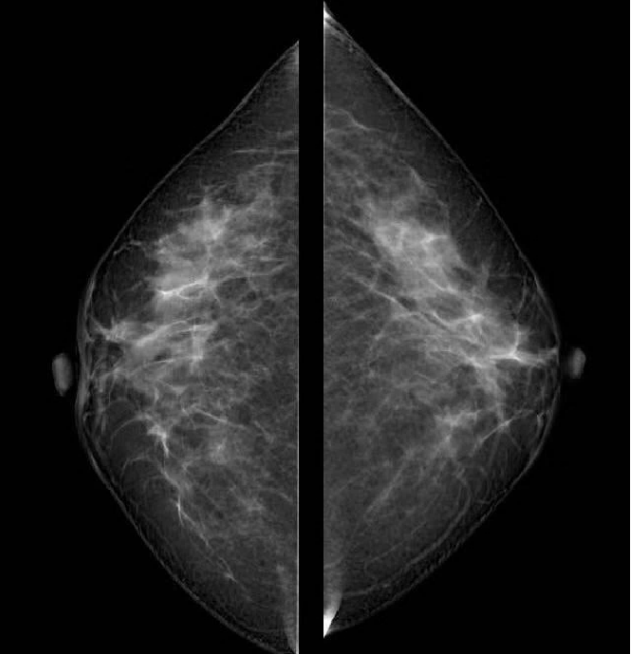

近年来,随着乳腺疾病逐渐增多,乳腺检查方法也日新月异,乳腺DR作为其中的一种检查方法应用较为广泛。日前,明光市中医院引进筛查和诊断乳腺疾病的“利器”——“联影-嫦娥3D”乳腺DR设备,能为广大群众朋友们提供精准的乳腺检查。

该设备具有高清、低剂量、断层三维融合数字成像的优势,可提高乳腺癌早期检出率并精准定位。

现代的乳腺X线检查设备不再是过去的二维成像,而是通过三维断层扫描,能更加清晰显示乳腺病灶及其所在的位置,精准度及灵敏性更高。